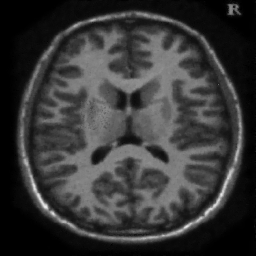

4.1. Uniform Gaussian noise

In this first experiment, we consider the denoising problem with brain scan images. The first set consists of images of pixels and Gaussian noise with zero mean and variance . The original and noisy images are shown in Figure 4.1. The domain decomposition-semismooth Newton algorithms run with the parameter values , , and . The results are shown in Figure 4.2. From the surface representation of , we can observe that is continuous and its shape is related to the one of the original image. In particular, the regularization is stronger in homogeneous regions in the image, and weaker where the image intensity undergoes variations on a smaller scale.